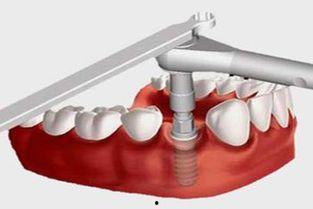

2. 切开牙龈:医生会在牙槽骨上切开一个小口,以便植入人工牙根。

3. 植入人工牙根:将人工牙根植入牙槽骨中,这个过程需要一定的技术,医生会小心翼翼地进行。

4. 缝合:完成人工牙根植入后,医生会缝合切口,并为你戴上临时牙冠。